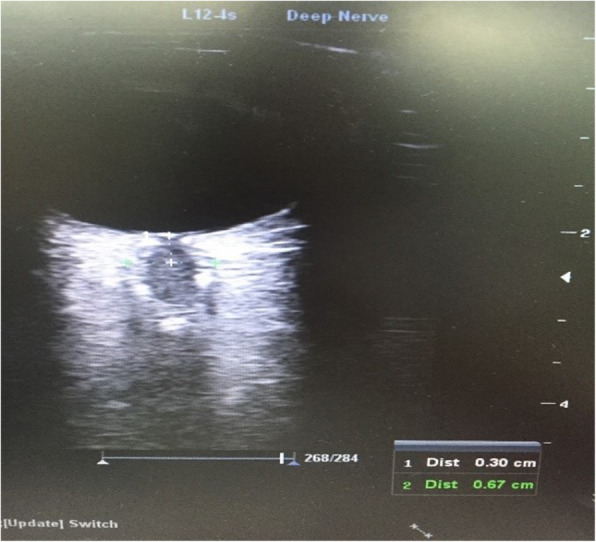

A 7 MHz linear probe and Mindray® Ultrasound device were used in this study. The measurements were taken by two PICU fellow experienced in the optic nerve ultrasonography, and the mean value of the measurements were calculated. During the measurements, the bedhead was adjusted to zero degrees, while the head of the patient was positioned at the midline. The measurements were performed in both eyes at regions 3 mm below the bulbs, while the eyes were closed, and the mean value of these measurements was calculated (Fig. 1). The INVOS® 5100C Cerebral Oximeter (Somanetics, Troy, MI) was used for the NIRS, which demonstrates the regional oxygenation level of the cerebral tissue (Fig. 2). NIRS measurements were made by a disposable sensor that placed on frontal area of head.

Fig. 1.

Ultrasonographic ONSD measurement